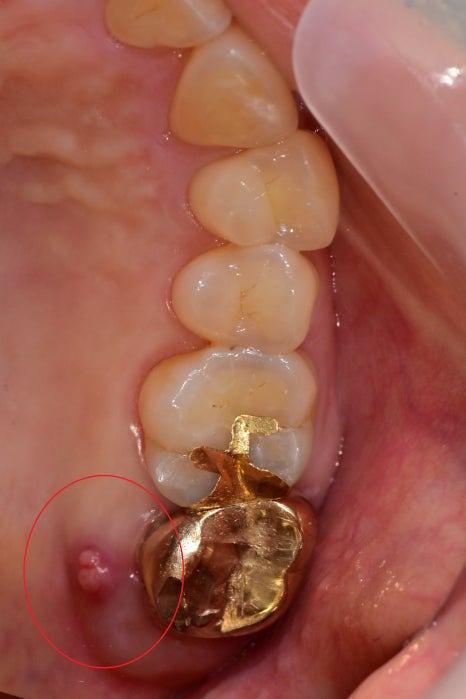

이미 엑스레이에서 근단부 염증이 심하시고, 입천장 쪽에는

고름 주머니까지 형성이 되어있었습니다.

동요도까지 생겨서 재 신경치료는 불가능해 보입니다.